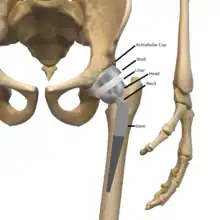

Implants

The prosthetic implant used in hip replacement consists of three parts: the acetabular cup, the femoral component, and the articular interface. Options exist for different people and indications. The evidence for a number of newer devices is not very good, including: ceramic-on-ceramic bearings, modular femoral necks, and uncemented monoblock cups.[76] Correct selection of the prosthesis is important.

Acetabular cup

The acetabular cup is the component which is placed into the acetabulum (hip socket). Cartilage and bone are removed from the acetabulum and the acetabular cup is attached using friction or cement. Some acetabular cups are one piece, while others are modular. One-piece (monobloc) shells are either ultra-high-molecular-weight polyethylene (UHMWPE) or metal, they have their articular surface machined on the inside surface of the cup and do not rely on a locking mechanism to hold a liner in place. A monobloc polyethylene cup is cemented in place while a metal cup is held in place by a metal coating on the outside of the cup. Modular cups consist of two pieces, a shell and liner. The shell is made of metal; the outside has a porous coating while the inside contains a locking mechanism designed to accept a liner. Two types of porous coating used to form a friction fit are sintered beads and a foam metal design to mimic the trabeculae of cancellous bone and initial stability is influenced by under-reaming and insertion force.[77] Permanent fixation is achieved as bone grows onto or into the porous coating. Screws can be used to lag the shell to the bone providing even more fixation. Polyethylene liners are placed into the shell and connected by a rim locking mechanism; ceramic and metal liners are attached with a Morse taper.

Femoral component

The femoral component is the component that fits in the femur (thigh bone). Bone is removed and the femur is shaped to accept the femoral stem with attached prosthetic femoral head (ball). There are two types of fixation: cemented and uncemented. Cemented stems use acrylic bone cement to form a mantle between the stem and to the bone. Uncemented stems use friction, shape and surface coatings to stimulate bone to remodel and bond to the implant. Stems are made of multiple materials (titanium, cobalt chromium, stainless steel, and polymer composites) and they can be monolithic or modular. Modular components consist of different head dimensions and/or modular neck orientations; these attach via a taper similar to a Morse taper. These options allow for variability in leg length, offset and version. Femoral heads are made of metal or ceramic material. Metal heads, made of cobalt chromium for hardness, are machined to size and then polished to reduce wear of the socket liner. Ceramic heads are more smooth than polished metal heads, have a lower coefficient of friction than a cobalt chrome head, and in theory will wear down the socket liner more slowly. As of early 2011, follow-up studies in patients have not demonstrated significant reductions in wear rates between the various types of femoral heads on the market. Ceramic implants are more brittle and may break after being implanted.

Articular interface

The articular interface is not part of either implant, rather it is the area between the acetabular cup and femoral component. The articular interface of the hip is a simple ball and socket joint. Size, material properties and machining tolerances at the articular interface can be selected based on patient demand to optimise implant function and longevity whilst mitigating associated risks. The interface size is measured by the outside diameter of the head or the inside diameter of the socket. Common sizes of femoral heads are 28 mm (1.1 in), 32 mm (1.3 in) and 36 mm (1.4 in). While 22.25 mm (7⁄8 in) was common in the first modern prostheses, now even larger sizes are available from 38 to over 54 mm. Larger-diameter heads lead to increased stability and range of motion whilst lowering the risk of dislocation. At the same time they are also subject to higher stresses such as friction and inertia. Different combinations of materials have different physical properties which can be coupled to reduce the amount of wear debris generated by friction. Typical pairings of materials include metal on polyethylene (MOP), metal on crosslinked polyethylene (MOXP), ceramic on ceramic (COC), ceramic on crosslinked polyethylene (COXP), and metal on metal (MOM). Each combination has different advantages and disadvantages.